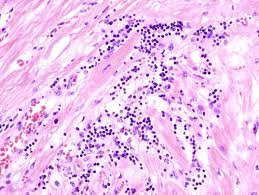

심근염(Myocarditis)은 심장 근육인 심근의 염증을 나타내며, 주로 바이러스, 박테리아, 기생충, 약물 반응 등의 인자로 인해 발생합니다. 이 염증은 심근 조직의 염증 세포와 면역 반응의 과도한 활성화로 인해 발생할 수 있습니다. 심근염은 심장 기능의 변화를 초래하며, 심장 파괴와 심부전과 같은 심각한 합병증을 유발할 수 있습니다.